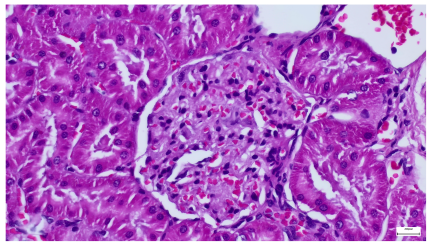

Table 4 below presents histological proof for renal damage in the G-IV group suffering from a dual metabolic impairment, albeit treated with statin.

Table 4.

Histological proof for renal damage in the diabetic-and-obese statin-treated group G-IV.

The histological extent of lesions suggests a definite inflammatory process in the renal matrix and glomeruli, but the extent of the disruptive process as resulting from an average nephron pool loss is limited. This is consistent with the limited duration of our experiment, with definite development of chronic kidney disease taking sometimes as long as 24 weeks. However, expecting this limited extent of damage, we chose a relatively short—proportionate—duration of statin treatment. Our results demonstrate a statistically significant higher retention of creatinine and urea in plasma—a reflection of the respective reduction in renal function—in every single experimental group (G-II to G-IV) in comparison to the control group G-I. The diabetic group G-III demonstrates the highest values for both creatinine and urea across the whole experiment population. The plasma concentrations of retention byproducts in both G-II and G-III are statistically significantly higher compared to the control G-I, indicating that each condition independently leads to important impairment in kidney function. The assumption of concurring actions in a model exhibiting obesity and diabetes simultaneously should translate into outcomes—renal and inflammatory—with values skewed from normality, the dimension of departure from the normal range at least as big as in any of the models exhibiting an individual condition.